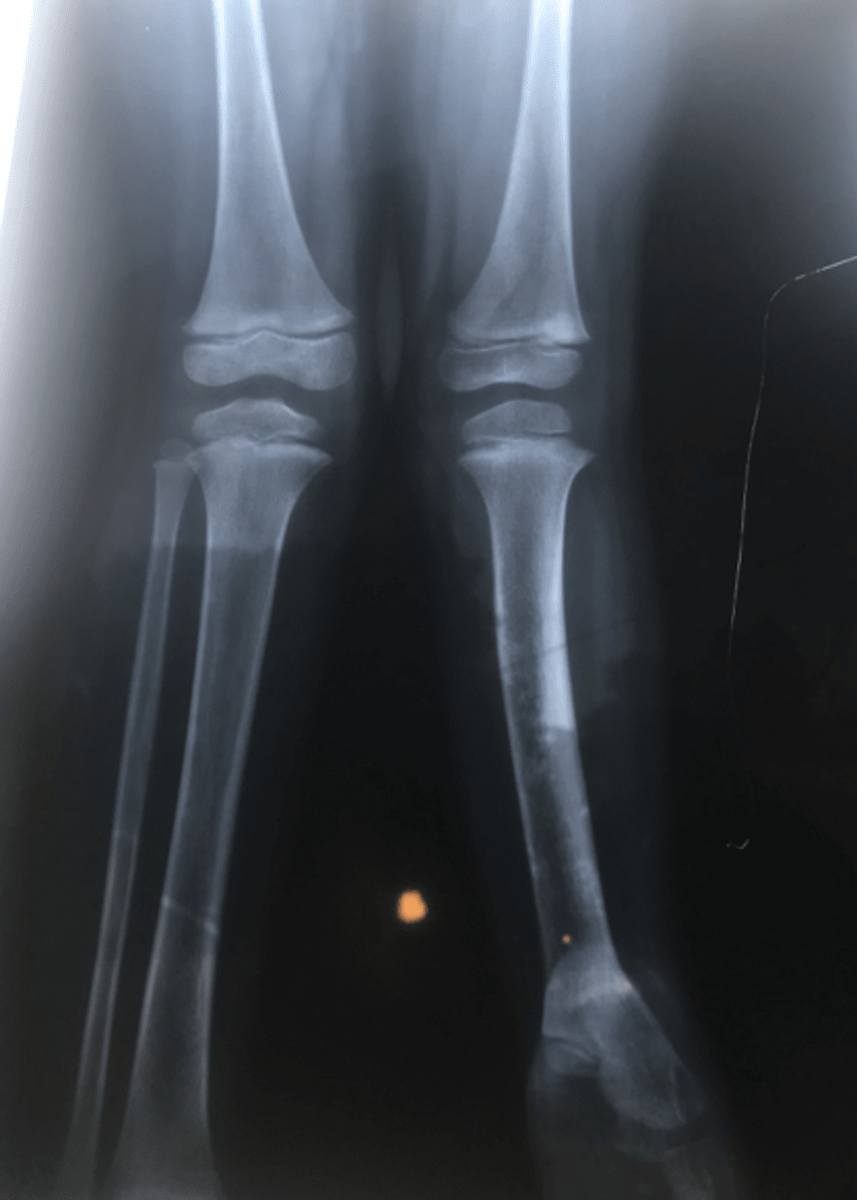

While in Haiti we spent two days in the clinic on the compound  with the clinic staff. The first day was education and the second day was to see some of the people in the community. I worked with Marlaine, RN and Dr. Lens.  Dr. Lens is a Haitian physician that sees patients one day a week in the clinic.   Marlaine is a registered nurse that would like to become a nurse practitioner.  I was asked to review a patients x-ray in which the child has one leg shorter than the other.